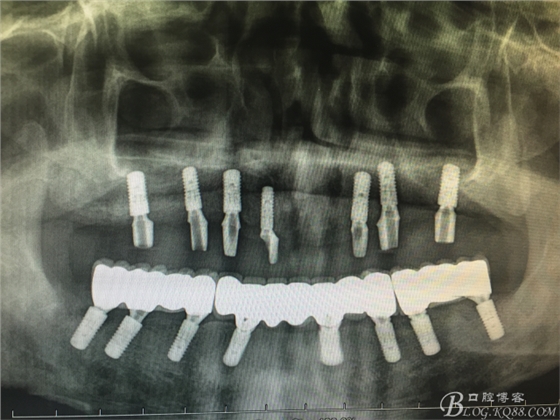

患者37歲 男 全口牙周病 手術(shù)一次完成 全程3小時全口種植修復(fù)全口種植修復(fù)全口種植修復(fù)全口種植修復(fù)全口種植修復(fù)全口種植修復(fù)全口種植修復(fù)全口種植修復(fù)全口種植修復(fù)全口種植修復(fù)全口種植修復(fù)全口種植修復(fù)全口種植修復(fù)全口種植修復(fù)全口種植修復(fù)